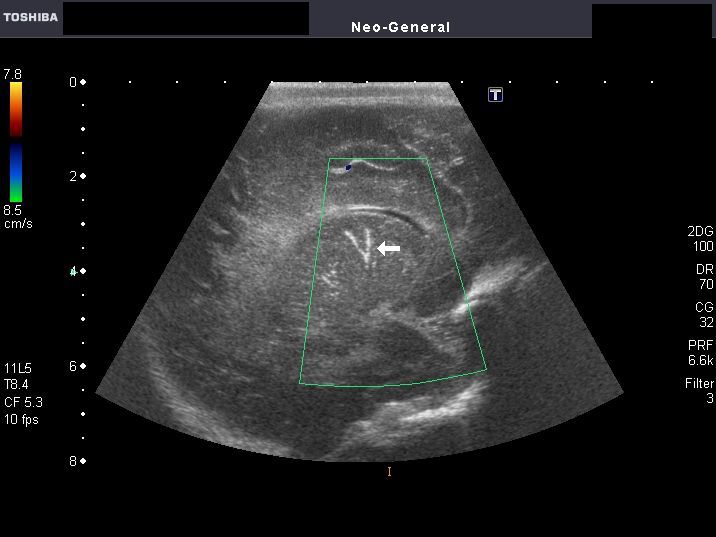

Periventricular leukomalacia in neonate

Multiple minute cystic lesions in white matter

This preterm neonate underwent sonography of the brain. Ultrasound images of the infant's brain revealed multiple small cystic lesions (2 to 3mm. size) the periventricular part of the deep white matter. Color Doppler image did not show any specific findings. These ultrasound appearances are diagnostic of Periventricular leukomalacia in the neonate's cerebral hemispheres. Periventricular leukomalacia can also present as markedly hyperechoic white matter. This condition is the result of chronic ischemic insult (chronic ischemia) of the infant's brain during immediate postnatal period (in preterm neonates).